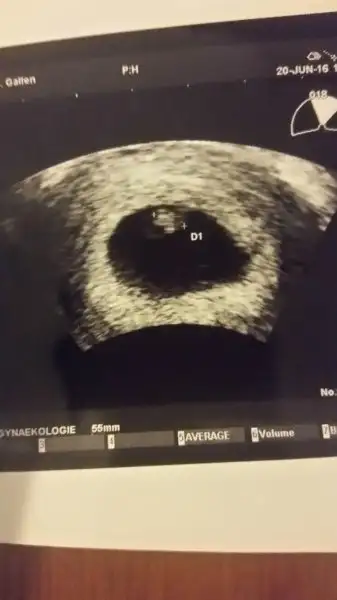

Bi yorum da benim minige rica edebilir miyiz? 7+3 batın usg. Tesekkurler:)Eki Görüntüle 1879196

Kese büyük ise kız küçük ise erkek ben geçmiş yorumlarina bakmişim.. doğru mu bilmiyorum. bazilarin tam tersi olabiliyo kişiden kişiye degişiyor.Eki Görüntüle 1879943 Kızlar bilen varsa yorum yapsın bari dundendir bekliyorum son adet tarihine göre 10 + 2 iki gün önce doktora gittim ultrasonda 11 haftalık çıktı

öle oluyormuş fasulye gibiyse erkek yuvarlak ise kızmiş:)Havalianne__ burda benim bebeğim 8+5 haftalık. Kese yuvarlaksa kız fasulye gibiyse erkek miydi. Benimki tam yuvarlak da değil tam fasulyede değil sanki. Ona göre bi bakar mısın

Karından baktı canımbenim sağda yatiyo karnimdan bakti. altinda duruyor sanirim erkek mi oluyorHavalianne__